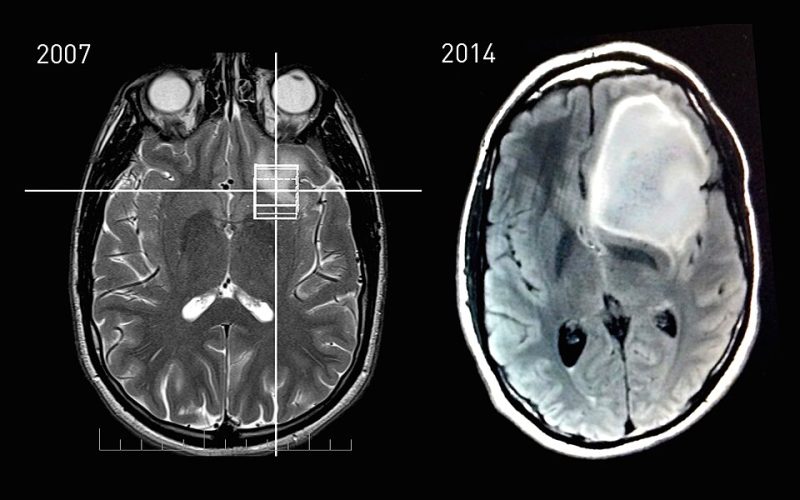

Untuk mendiagnosis astrositoma, dokter biasanya melakukan pemeriksaan neurologis terlebih dahulu. Jika ditemukan indikasi adanya gangguan, pasien akan menjalani pemeriksaan pencitraan seperti MRI (Magnetic Resonance Imaging) atau CT scan untuk melihat adanya massa di otak.